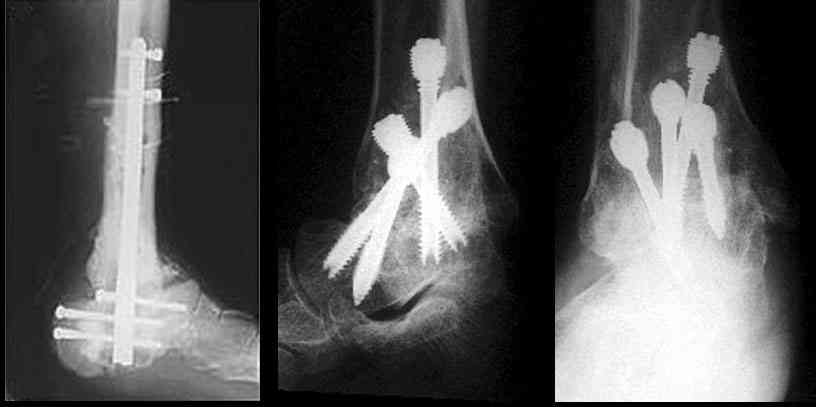

Можно: 65-летняя пациентка, оперирована по поводу несросшегося в гипсе перелома лодыжек с патологической вальгусной установкой стопы и выраженным нарушением опрной функции. Оперирована через 6 месяцев после травмы. Рентгенограммы через 4 месяца после операции.

С уважением, А.Семенистый.

Уважаемый А.Семенистый. Складывается впечатление, что вы выполнили трехсуставный артродез, уж больно длинные блокирующие винты. Не мешают ли они пациентке при ходьбе?

Да конечно винты длинноваты! Мешают ли ходить? Во всяком случае субьективно пациентка удовлетворена. Ходит, естевственно, хуже чеи до травмы, но намного лучше, чем до операции.